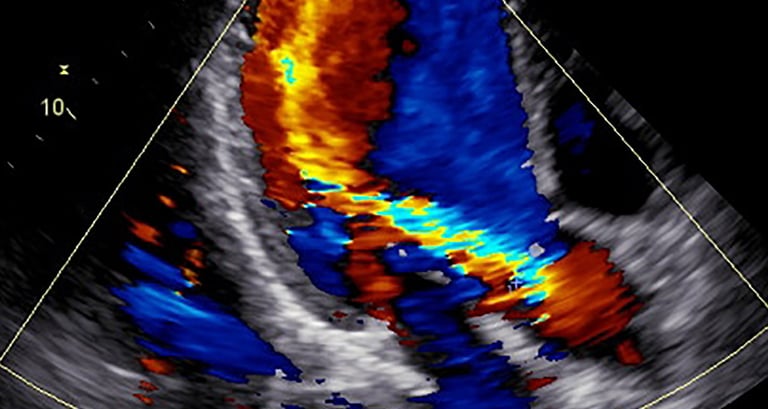

ECODOPPLER CARDÍACO COLOR

También llamado doppler cardíaco, o ecocardiograma, realizado por el dr. morisse para el diagnóstico de múltiples patologías cardiovasculares, evaluación deportiva, estudio de soplos y demás indicaciones de diversa índole cardiovascular. gran utilidad clínica